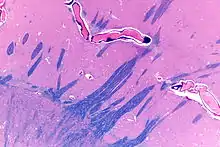

Pallidal nuclei are made up of the same neuronal components. In primates, almost all pallidal neurons are very large, parvalbumin-positive, with very large dendritic arborizations. These have the peculiarity of having the three-dimensional shape of flat discs, parallel to one another, parallel to the border of the pallidum[3] and perpendicular to the afferent striatopallidal axons.[4] There are only a few small local circuitry neurons.

The globus pallidus is traversed by the numerous myelinated axons of the striato-pallidonigral bundle that give it the pale appearance from which it is named.

The ultrastructure is very peculiar, as the long dendrites are everywhere, without discontinuity, covered by synapses.[5][6]